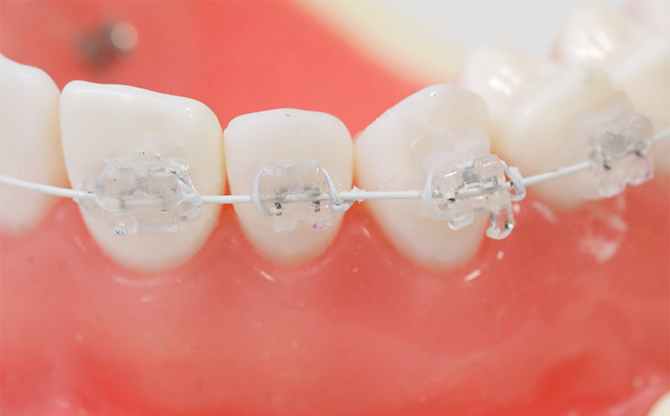

ワイヤー矯正も、透明のブラケット装置と白いワイヤーで目立ちにくいです。

表側矯正(ワイヤー矯正)

多くの症例に適合する実績ある治療法

歯の表面にブラケットを接着し、ワイヤーを通して歯を動かします。ワイヤー矯正は歴史が長く、実績もあり、大きく歯を動かすことができるため、幅広い症例に対応が可能です。